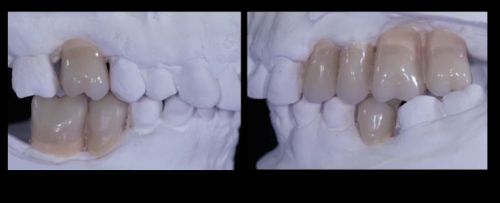

3.Когда принято решение, изготавливается восковая модель, отображающая желаемое положение края десны, форму коронки/коронок и зубодесневых сосочков. По дубликату такой модели создают хирургический шаблон; таким образом, имплантолог может четко позиционировать имплантат/имплантаты.

Фото. Восковая модель.